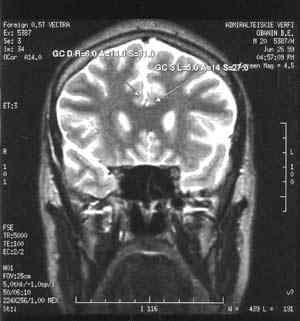

Рассеянный склероз - тяжелое хроническое заболевание головного и спинного мозга, поражающее сравнительно молодых людей 20 - 40 лет. Неясность многих вопросов возникновения и механизмов развития заболевания, трудности диагностики на ранних стадиях развития, разнообразие клинических вариантов течения с быстрой инвалидизацией, отсутствие эффективных методов лечения вывели изучение рассеянного склероза в круг наиболее актуальных задач современной медицины. В лаборатории нейроиммунологии Института мозга человека РАН разработан новый подход, позволяющий одновременно с использованием специфичных иммунологических методов оценки поражения клеток центральной нервной системы применять магнитно-резонансную и позитронно-эмиссионную томографию для визуализации патологического процесса. Принципиальная новизна состоит в том, что данный подход позволяет одновременно оценивать как системные аутоиммунные нарушения при рассеянном склерозе, так и локальные функциональные и морфологические изменения в центральной нервной системе. Комплексное нейроиммунологическое, инструментальное, клиническое обследование пациентов с рассеянным склерозом позволило установить важную роль поражений коры и подкорковых структур в механизмах развития этого заболевания.

Разрешить это противоречие возможно с применением стереотаксической техники. Стереотаксис - наукоемкая медицинская технология, обеспечивающая возможность малотравматичного, щадящего, прицельного доступа к глубоким структурам головного мозга и дозированное воздействие на них. Стереотаксис вомногом - нейрохирургия будущего, он способен заменить целый ряд “открытых” нейрохирургических вмешательств с широкими костно-пластическими трепанациями на малотравматичные щадящие воздействия.

Современная нейрохирургия использует проверенные временем методики точной локализации поражения в мозге и сегодня это, в первую очередь, осуществляется методами магниторезонансной томографии, разрешение которой перекрывает потребности для определения места хирургического вмешательства. В типичных условиях современной клиники http://госпиталь.укр/нейрохирургия выполняется практически весь спектр нейрохирургической помощи, включая самые современные методы локализации места воздействия.

Суть стереотаксиса: очень точно знать, где в мозге находится структура (мишень), на которую необходимо воздействовать - коагулировать, заморозить, эвакуировать, стимулировать, и через маленькое отверстие в черепе - около сантиметра - ввести тонкий, около двух миллиметров в диаметре, инструмент, который чаще не прокалывает, а как бы раздвигает ткань мозга с минимальным травматическим воздействием. На конце этого инструмента размещен эффектор, который и производит необходимое воздействие. При этом еще исключительно важно точно попасть инструментом в структуру-мишень.

В развитых странах, прежде всего в США, клинический стереотаксис занял достойное место в нейрохирургии. В настоящее время в США насчитывается около 300 нейрохирургов-стереотаксистов, членов Американского стереотаксического общества. Основа стереотаксиса - математика и точные приборы, обеспечивающие прицельное погружение в мозг тонких инструментов. Важную роль в стереотаксисе играют современные методы и приборы интроскопии, которые позволяют “заглянуть” в мозг живого человека. Как указывалось выше, это - позитронно-эмиссионная томография, магнито-резонансная томография, компьютерная рентгеновская томография. “Стереотаксис- мерило методической зрелости нейрохирургии” - мнение ныне покойного нейрохирурга Л.В.Абракова. И, наконец, очень важно для стереотаксического метода лечения знание роли отдельных ядер, «точек» в мозге человека, понимание их взаимодействия, т.е. знание того, где и что именно нужно сделать в мозге для лечения той или иной болезни.

Стереотаксический аппарат Лаборатория стереотаксических методов Института мозга человека РАН под руководством д.м.н. лауреата Государственной премии СССР А.Д.Аничкова - ведущий стереотаксический центр России. Здесь родилось самое современное направление стереотаксиса - компьютерный стереотакcис с программно-математическим обеспечением, реализуемым на ЭВМ (до этих разработок стереотакси-ческие расчеты проводились нейрохирургами во время операции, или же больной в травматичной раме должен был непосредственно перед операцией подвергаться интроскопии (МРТ или КТ)). Здесь же разработаны десятки стереотаксических приборов, некоторые из которых прошли клиническую апробацию и с помощью которых решались самые сложные задачи стереотаксического наведения. Совместно с коллегами из ЦНИИ “Электроприбор” создана и впер-вые в России серийно выпускается компьютеризированная стереотак-сическая система, которая по ряду основных показателей превосходит аналогичные зарубежные образцы. “Наконец робкие лучи цивилизации осветили наши темные пещеры”, - неизвестный автор.

В нашем Институте стереотаксис применяется при лечении больных, страдающих двигательными нарушениями (болезнью Паркинсона, хореей Гентингтона, другими гемигиперкинезами и др.), эпилепсией, неукротимыми болями (в частности фантомно-болевым синдромом), некоторыми психическими нарушениями. Кроме того, стереотаксис может применяться и применяется для уточненной диагностики и лечения некоторых опухолей головного мозга, лечения гематом, абсцессов, кист мозга. Важно подчеркнуть, что стереотаксические вмешательства (как и все остальные нейрохирургические вмешательства) предлагаются больному только в том случае, если исчерпаны все возможности нехирургического (медикаментозного) лечения, и само заболевание представляет для пациента опасность (или лишает его трудоспособности, десоциализирует его). Естественно, что все операции производятся в клинике ИМЧ только при согласии больного и его родственников, после консилиума специалистов разного профиля.

Можно говорить о двух видах стереотаксиса. Первый, нефункциональный, применяется тогда, когда в глубине мозга имеется какое-то органическое поражение. Например, опухоль. При попытке ее удаления с помощью обычной техники придется проходить через здоровые, выполняющие важные функции структуры, и больному может быть нанесен вред, иногда даже несовместимый с жизнью. Однако эта опухоль хорошо видна с помощью современных средств интровидения: магниторезонансного и позитронно-эмиссионного томографов. Можно рассчитать ее координаты и разрушить ее, или, например (еще один метод, развиваемый в ИМЧ), ввести с помощью малотравматичного тонкого щупа радиоактивные источники, которые выжгут опухоль и за это же время распадутся. Повреждения при проходе сквозь мозговую ткань минимальны, будет уничтожена только опухоль, причем иногда очень сложной формы, очень агрессивная, и уничтожена радикально. Мы провели ряд таких операций несколько лет назад, и до сих пор живут больные, у которых при традиционных методах лечения не было никакой надежды.

Стереотаксическая операцияСуть этого метода в том, что мы устраняем «дефект», который четко виден. Задача состоит в том, как до него добраться, какой путь выбрать, чтбы не задеть важные зоны, какой адекватный метод устранения «дефекта» выбрать: имплантацию источников, термокоагуляцию или криодеструкцию, но суть одна: мы устраняем то, что четко видим.